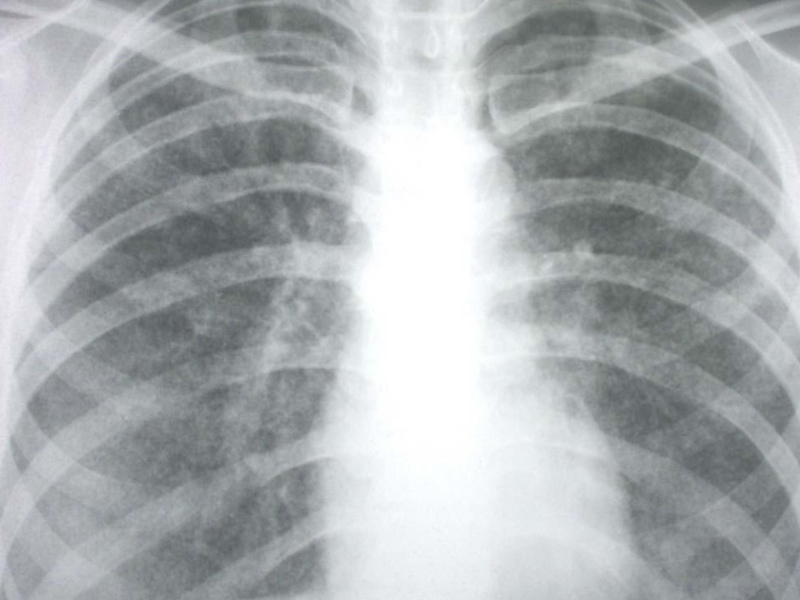

Рентгенологически симметрично в обоих легких, преимущественно в верхних и

средних отделах, обнаруживаются в одних случаях однотипные средние, в других

– крупные очаги.

При крупноочаговых процессах определяются очаги до 1 см, округлой или неправильной формы без резких очертаний, в верхних отделах могут обнаруживаться отдельные или множественные тонкостенные (штампованные) каверны, которые в части случаев выявляются только при томографическом исследовании.

В редких случаях лимфогенного диссеминированного туберкулеза очаги располагаются в средних отделах на фоне выраженной сетчатой и линейной тяжистости. Корни легких и при гематогенной и лимфогенной диссеминации обычно нерезко расширены.